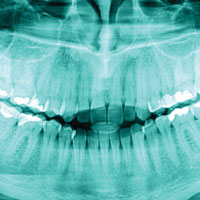

3D x-ray image capture

Using advanced imaging systems, our dentists can capture detailed 3D x-ray images of your dental anatomy. This high-resolution imaging helps support clinicians in accurately diagnosing anomalies and creating individual tailored treatment plans.

3D x-ray image capture may be used in treatments such as:

Check-ups

Dental implants